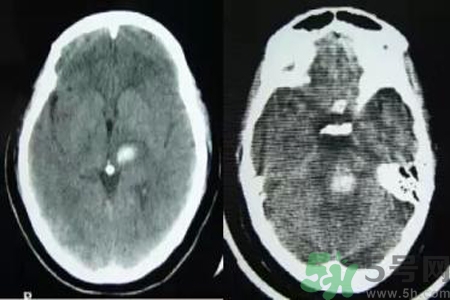

腦出血也稱腦溢血。顧名思義,腦出血是指腦實質(zhì)內(nèi)的血管破裂,血液溢出即為腦出血。那么腦出血的發(fā)病因素是什么?腦出血的并發(fā)癥有哪些?

引起腦出血的病因很多,最常見的病因是高血壓動脈粥樣硬化,其次為先天性腦血管畸形或動脈瘤、血液病、腦外傷、抗凝或溶血栓治療、淀粉樣血管病等引起的腦出血。根據(jù)病因分類如下。

微動脈瘤破裂

因腦內(nèi)小動脈壁長期受高血壓引起的張力影響,使血管壁薄弱部位形成動脈瘤,其直徑一般500μm。高血壓患者的腦內(nèi)穿通動脈上形成許多微動脈瘤,多分布在基底核的紋狀動脈、腦橋、大腦白質(zhì)和小腦中直徑在100~300μm的動脈上。這種動脈瘤是在血管壁薄弱部位形成囊狀,當(dāng)血壓突然升高時,這種囊性血管容易破裂造成腦出血。